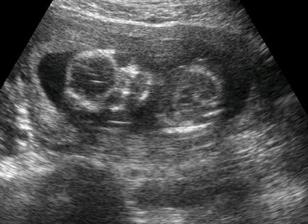

Testy + utz + bříško ♥